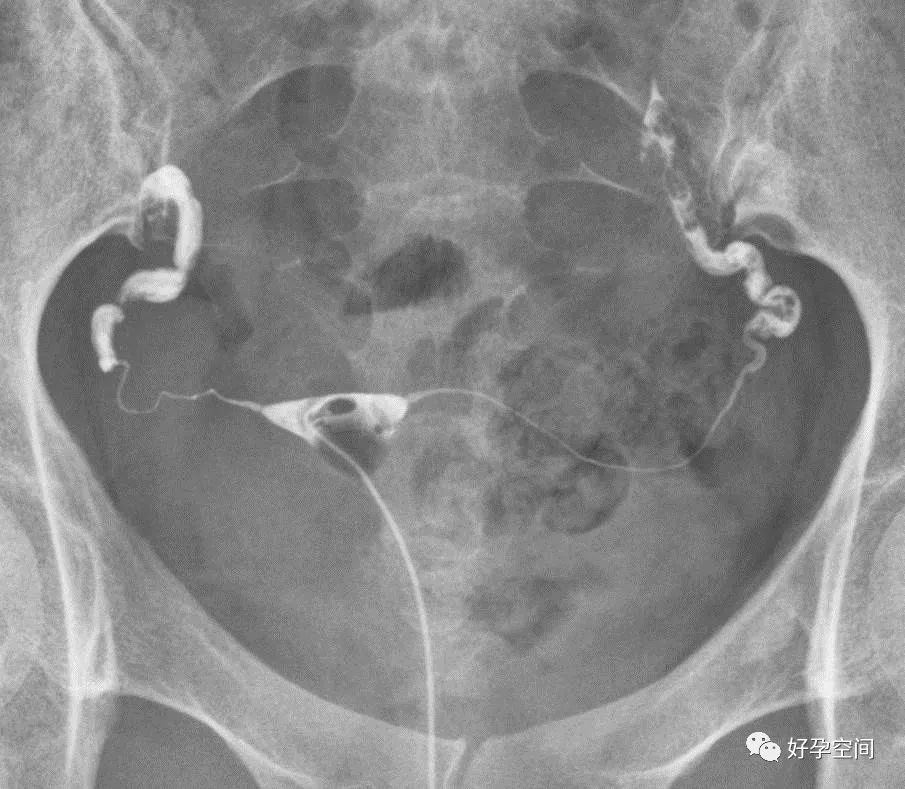

弥散相,延迟5分钟摄片,双侧输卵管内可见较多造影剂

弥散相,延迟10分钟摄片,双侧输卵管内可见少量造影剂

弥散相,延迟20分钟摄片,双侧输卵管内基本没有造影剂残留